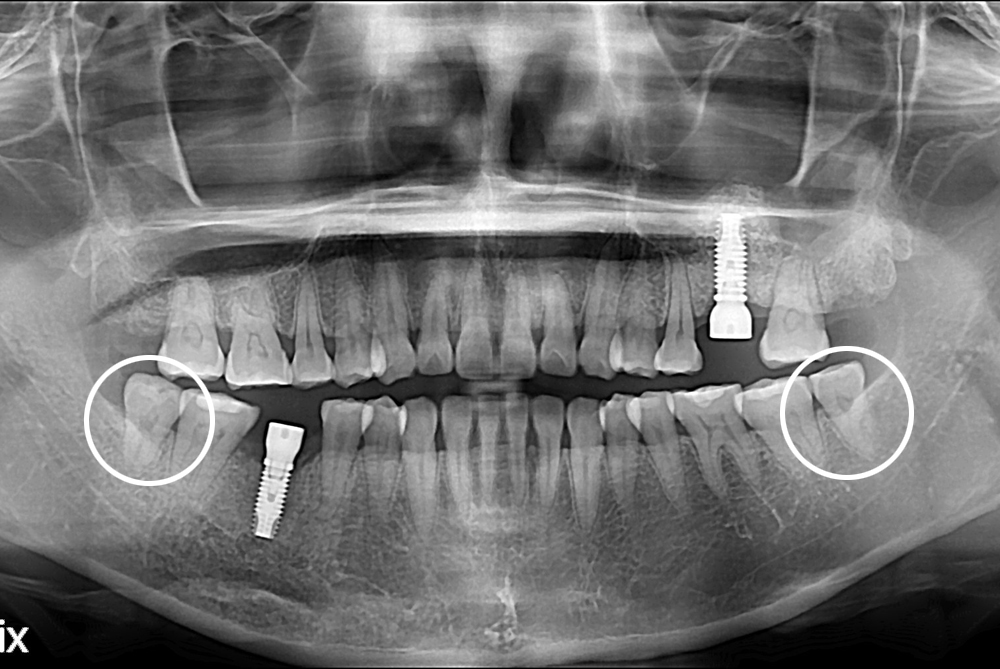

치료후 : 2017-05-24

세종치과는 구강악안면외과학 박사이신 원장님이 발치하는 치과입니다.